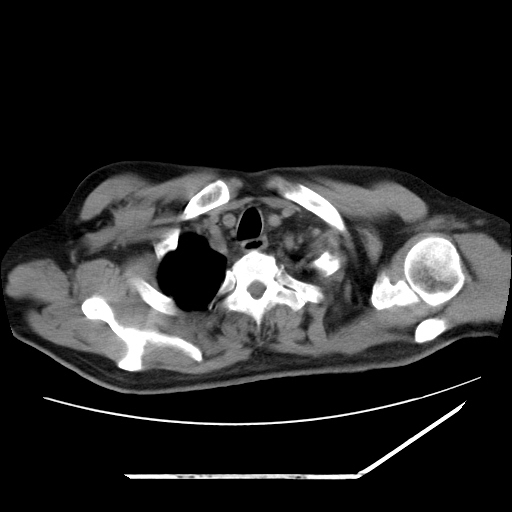

男,57,畏寒,发热

双肺多发结节样病灶,部分内见透光区,纵隔内见淋巴结肿大。结核临床如有畏寒,高热,白细胞增高首先考虑迁徙性肺脓肿(多是金黄色葡萄球菌感染)。

注意除外转移瘤。

肺多发结节样病灶,部分内见透光区,纵隔内见淋巴结肿大。结核临床如有畏寒,高热,白细胞增高首先考虑迁徙性肺脓肿(多是金黄色葡萄球菌感染)。